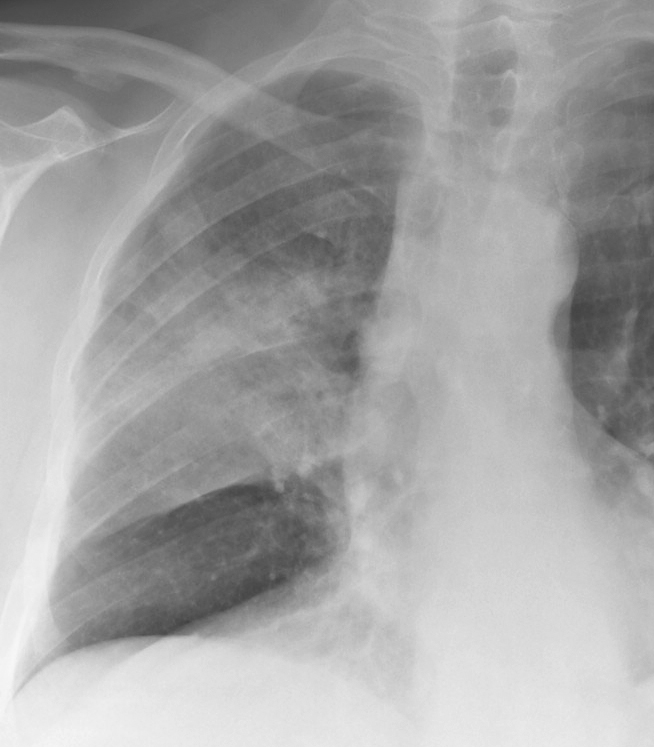

Gallery Lung Cancer BAC BAC Case 1 PA

BAC Case 1 PA